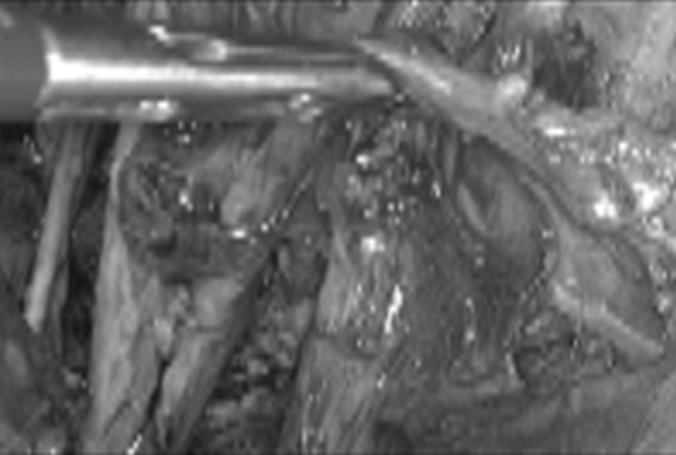

We analyzed 4 patients who underwent laparoscopic radical trachelectomy for early-stage cervical cancer between December 2011 and May 2013.

Four patients were included in this study. Total laparoscopic radical trachelectomy was performed in all cases. The mean age was 26 years (range, 19-32 years), the mean body mass index was 21 (range, 18-23), and the mean length of hospital stay was 33 hours (range, 24-36 hours). The mean operative time was 225 minutes (range, 210-240 minutes), and no complications were reported. During the postoperative period, only 1 patient presented with left vulvar edema, which resolved spontaneously. The pelvic and parametrial lymph nodes, as well as the vaginal cuff and cervical resection margins, were negative for malignancy in all cases. On average, 18 pelvic lymph nodes (range, 15-20) were removed. The tumor stage was IB in all 4 patients, and the mean tumor size was 17 mm (range, 12-31 mm). No patient required conversion to laparotomy.